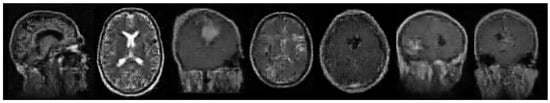

3.1. Dataset

3.2. Data Loading and Preparation